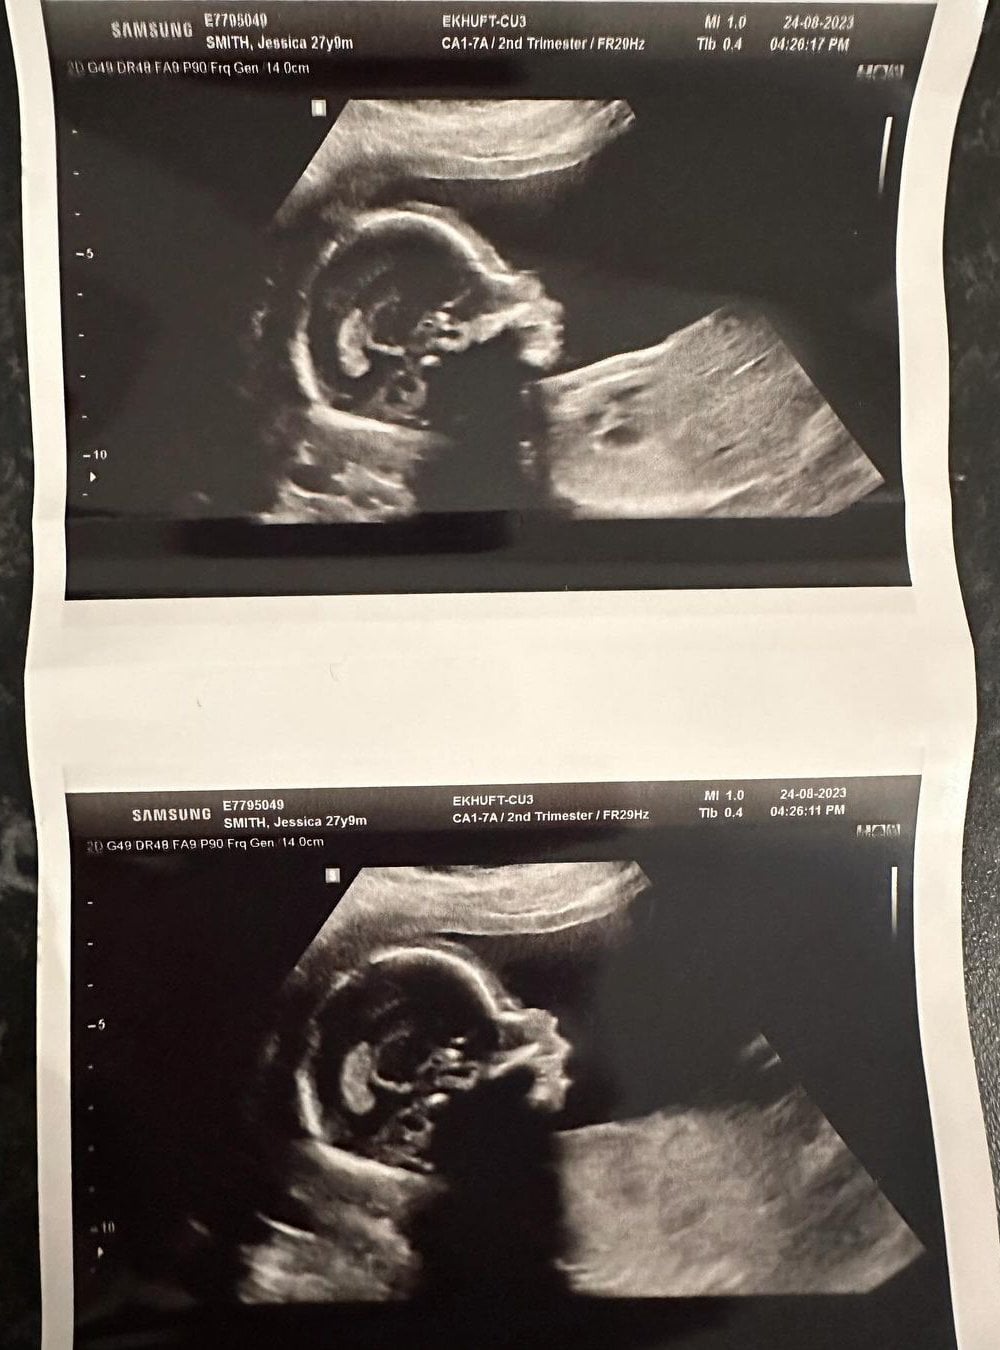

Uzun süredir Rick Latham ile birlikte olan Smith, bebeğinin ultrason görüntüsünü paylaştı.